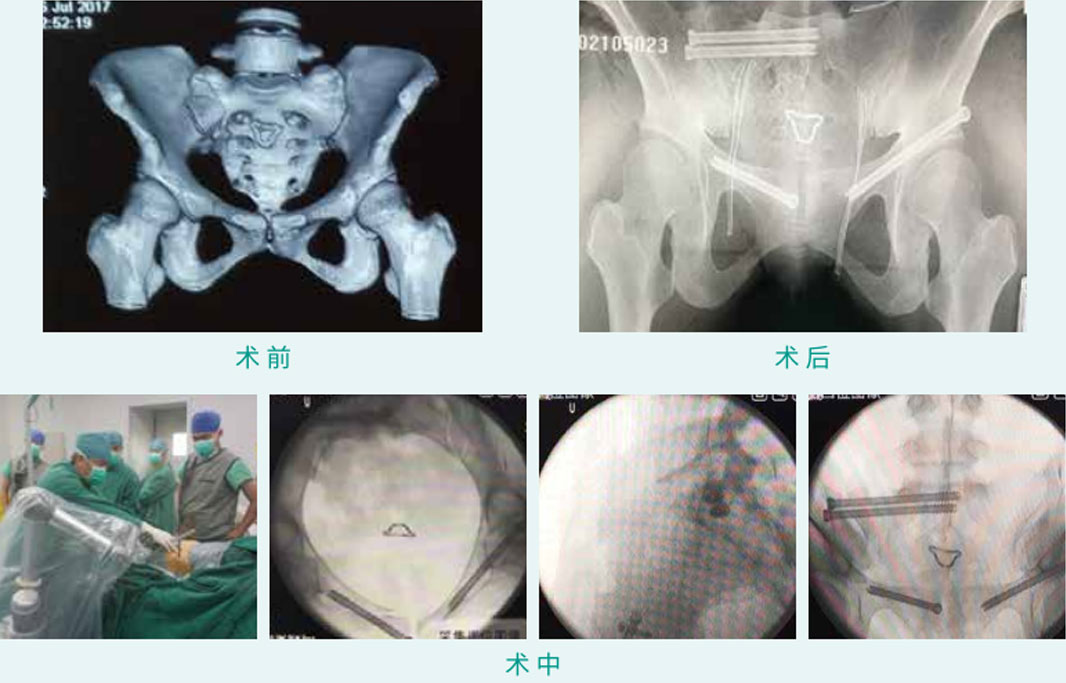

TiRobot ? Sacroiliac Joint (S1) and Bilateral Superior Ramus of Pubis Percutaneous Screw Fixation

天玑? 辅助骶髂枢纽(骶1)及双侧前柱经皮空心螺钉内牢靠术

基本情形:患者女,,,,,,,33岁,,,,,,,骨盆骨折

机械人累积用时:30分钟

植入物:4枚空心螺钉

病例泉源:北京积水潭医院 苏永刚